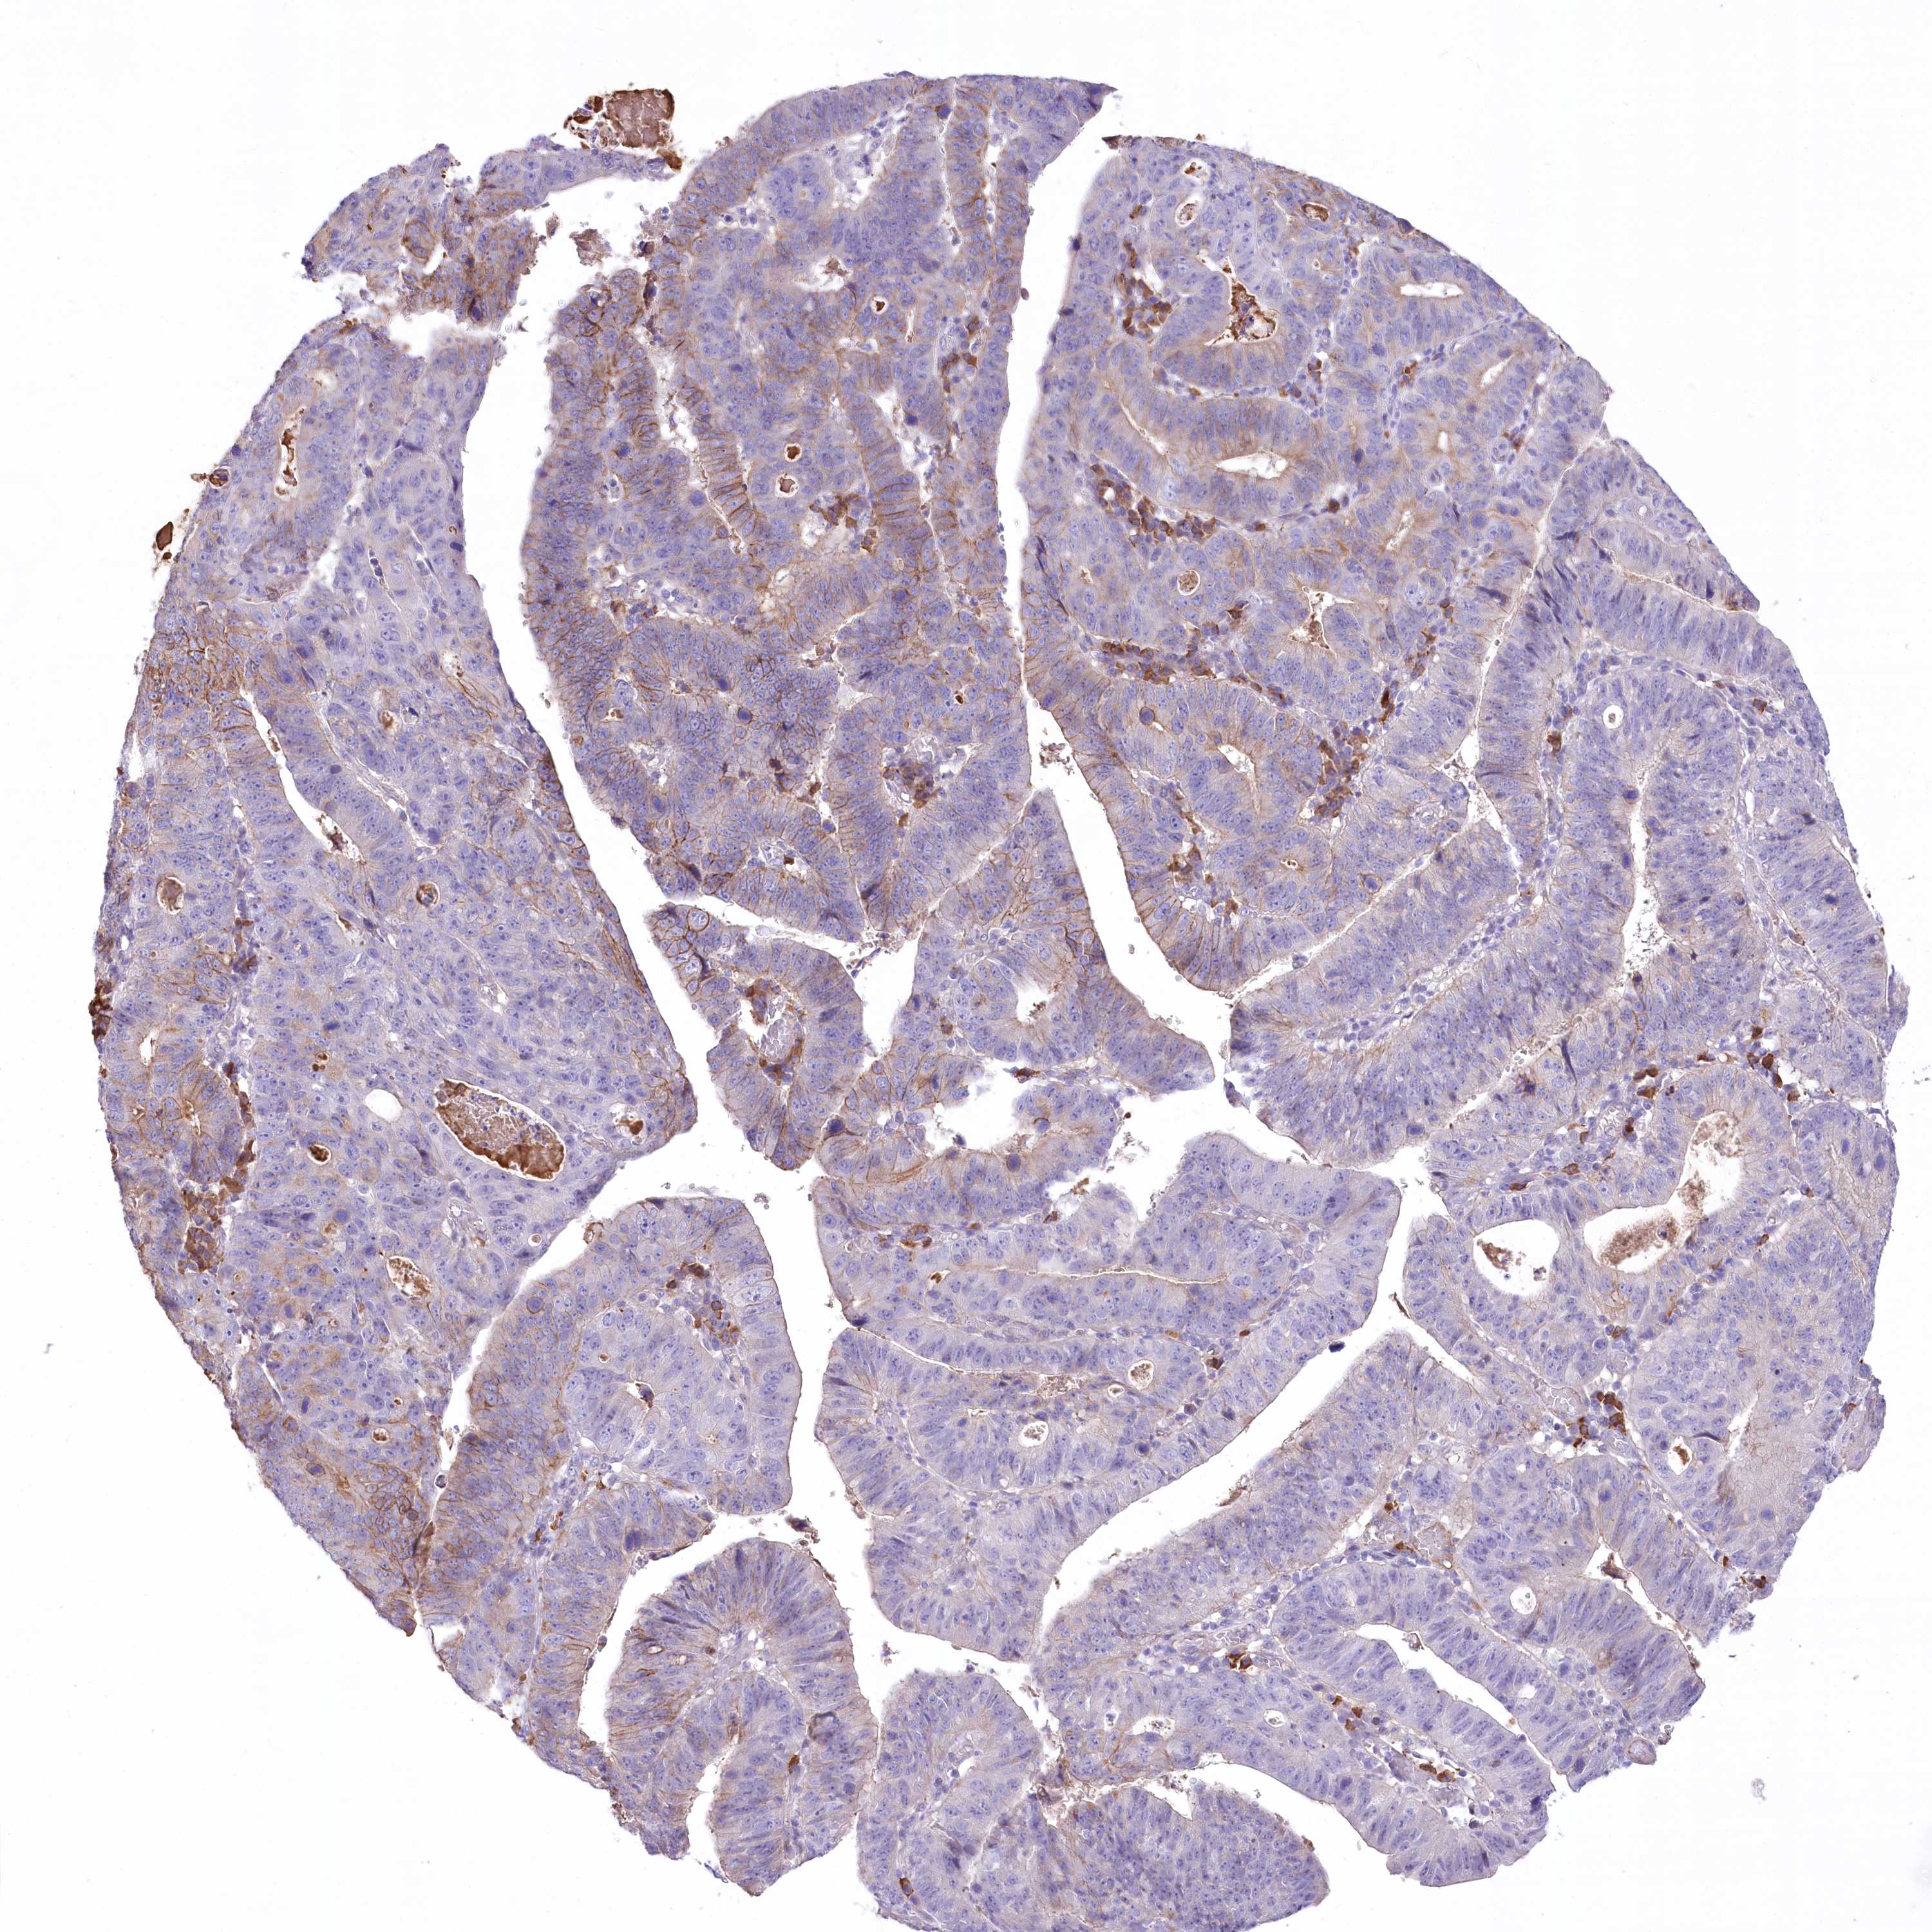

STOMACH CANCER - Protein expressioni

A mouse-over function shows sample information and annotation data. Click on an image to view it in a full screen mode. Samples can be filtered based on level of antibody staining by selecting one or several of the following categories: high, medium, low and not detected. The assay and annotation is described here.

Note that samples used for immunohistochemistry by the Human Protein Atlas do not correspond to samples in the TCGA dataset.

Antibody stainingi

Antibody staining in the annotated cell types in the current human tissue is reported as not detected, low, medium, or high, based on conventional immunohistochemistry profiling in selected tissues. This score is based on the combination of the staining intensity and fraction of stained cells.

Each image is clickable and will lead to virtual microscopy that enables deeper exploration of all samples and also displays staining intensity scores, fraction scores and subcellular localization as well as patient and tissue information for each sample.

Antibody HPA037605

Antibody HPA037606

Staining

High

Medium

Low

Not detected

Intensity

Strong

Moderate

Weak

Negative

Quantity

>75%

75%-25%

<25%

None

Location

Nuclear

Cytoplasmic/membranous

Cytoplasmic/membranous,nuclear

Adenocarcinoma, NOS